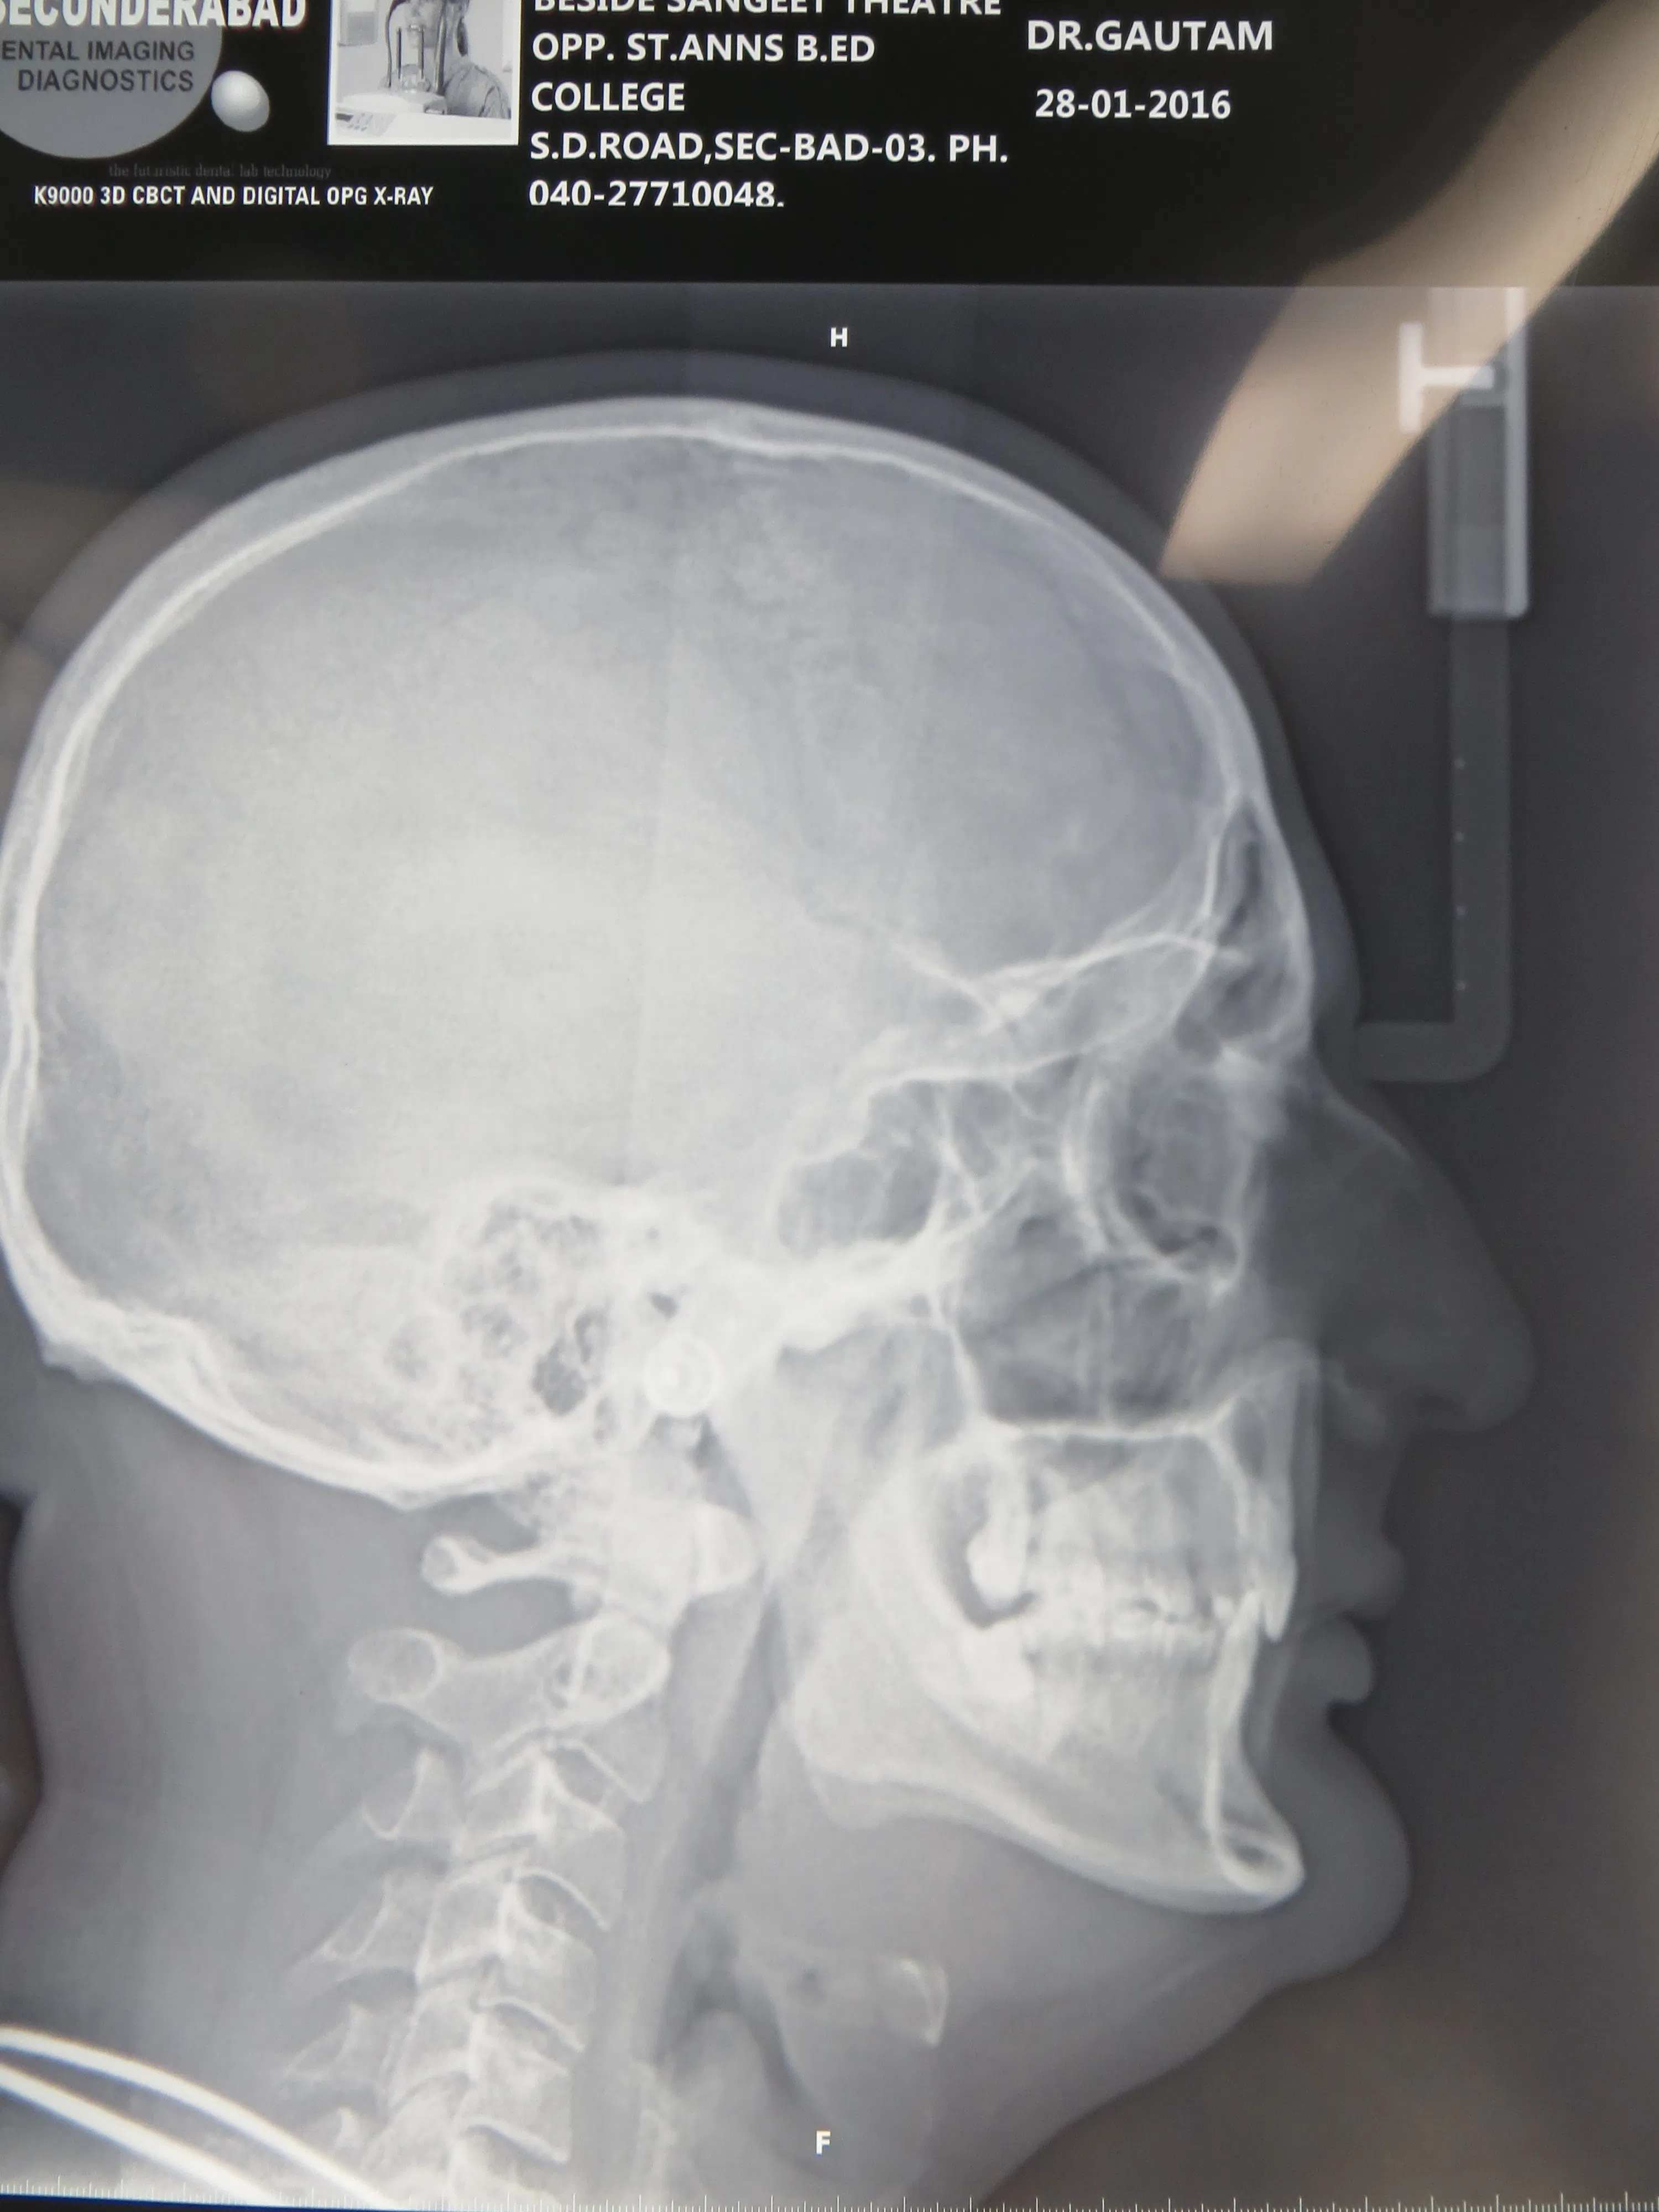

ORTHOGNATHIC AND COSMETIC SURGERY

Do you feel your jaws are not in alignment? Are your jaws very prominent or very retrusive? Do you want your chin to be more prominent? All these problems can be addressed with a proper assessment, xrays and corrective surgery. Improve your confidence and self esteem with cosmetic orthognathic surgery.